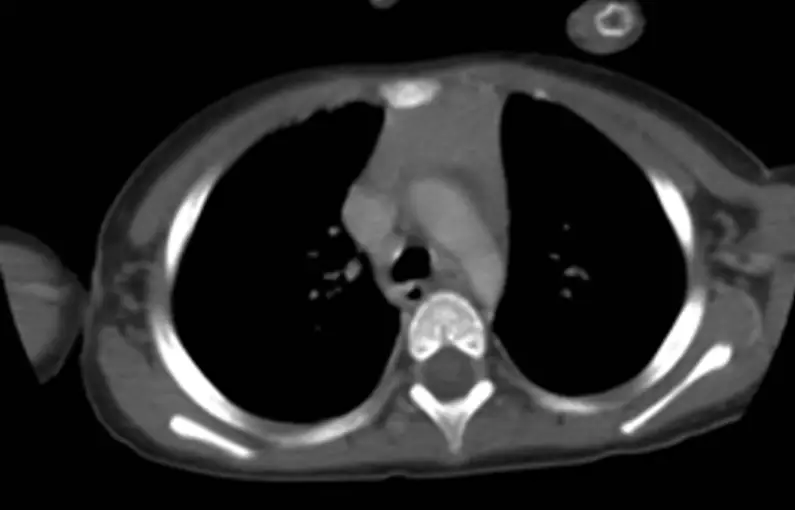

2歲女童因咳嗽就醫,由於胸部 X 光顯示縱膈腔變寬,因此在接受對比劑注射後,接受電腦斷層掃描檢查如圖,在主動脈弓之前可見明顯軟組織,其最常見原因為何?

- 影像顯示一塊位於主動脈弓(aortic arch)之前的均質軟組織密度結構

- 邊緣光滑、形態呈 quadrilateral/triangular,無壓迫周邊組織或氣管、血管的擠位現象 (no mass effect)

- 與上下胸腺組織連續,無囊性低密度(fat/fluid)區、鈣化或異質性增強

符合生理性或正常增大胸腺的典型 CT 特徵:在幼童(<5 歲)時,胸腺呈 quadrilateral,邊緣凸出,對比增強後均一顯影,密度與肌肉相近 (thoracickey.com)。